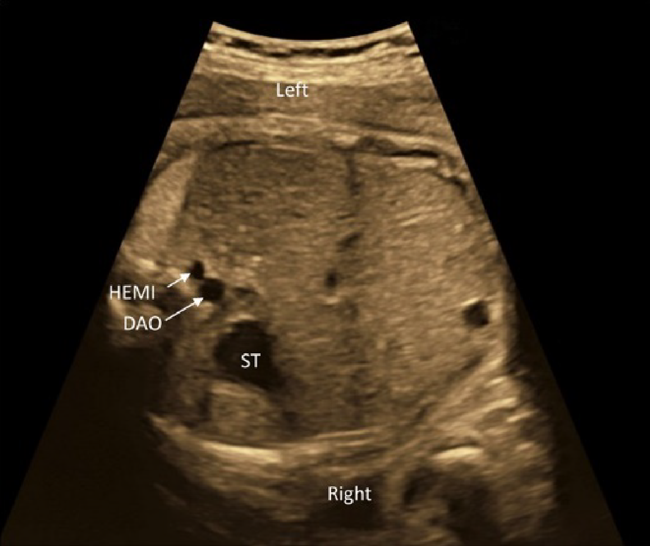

(1) Abdominal Cross-Section

The laterality of the fetus must be determined unequivocally. The gastric bubble is to be found on the left side of the body, the aorta on the left of the spinal column, and the inferior vena cava on the right. The inferior vena cava should be connected to the right atrium. Abnormal relationship between these structures is often the case in heterotaxy syndrome. Total anomalous pulmonary venous return of an infracardiac type may present an abnormal blood vessel (a vertical vein) in the abdominal cross-section.